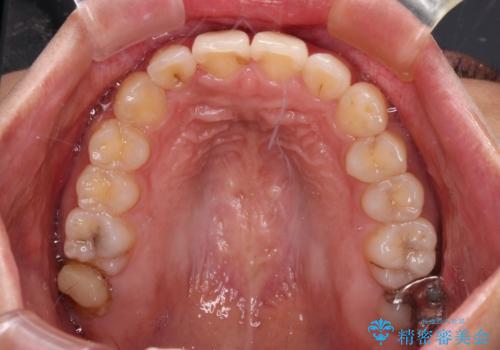

【モニター】歯列が狭くデコボコが気になる 急速拡大装置を用いたインビザライン矯正

上顎骨の幅が下顎骨よりも小さいので、拡大装置により骨幅を広げて上下関係を改善し、その後インビザラインにて歯並びを整えることとしました。

上下の骨幅を改善したことで、スムーズに歯列矯正を行うことができました。

土台のまま放置されていた歯は土台の状態で咬み合っていましたが、急速拡大を行った際に咬み合わせが著しく挙上されたため、その際に土台を大きくすることで咬み合う歯との距離を確保しました。